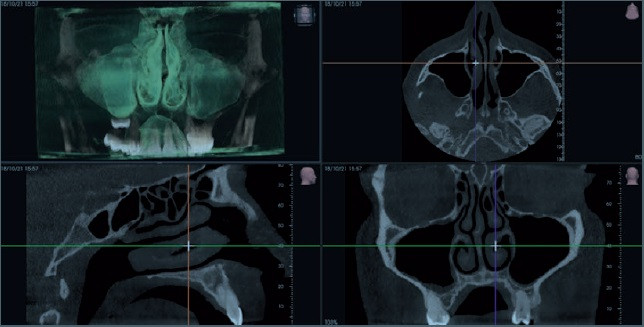

CORE 1000 biedt een breed scala aan volumetrische groottes, elk ontworpen voor specifieke behoeften. Met speciale FOV's, filters, geoptimaliseerde protocollen en Scout View halen gebruikers het maximale uit hun apparatuur en genieten van steeds betere prestaties.

Met de zeer flexibele geavanceerde oplossingen van CORE kan men zelfs de de meest complexe morfologieën onderzoeken, zelfs de kleinste anatomische details vastleggen en mogelijke positioneringsfouten van de patiënt corrigeren.